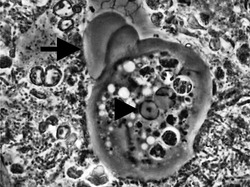

Entamoeba gingivalis from periodontal pocket [1]

Entamoeba gingivalis from aggressive periodontal disease patient biofilm using phase contrast microscope 1000x. It is recognizable through its dense core in the middle, formed by a central point encircled by a circular halo and surrounded by bigger phagosomes inside a greyish cytoplasm.

It is found in the mouth[5] inside the gingival pocket biofilm near the base of the teeth, and in periodontal pockets.[1] Entamoeba gingivalis is found in 95% of people with gum disease and rarely in people with healthy gums.[6][7] Cyst formation is not present; therefore transmission is direct from one person to another by kissing, or by sharing eating utensils. Only the trophozoites are formed and the size is usually 20 micrometers to 150 micrometers in diameter. Entamoeba gingivalis have pseudopodia that allow them to move quickly and phagocytise the nucleus of polynuclear neutrophils by exonucleophagy in periodontal disease.[8] Their spheroid nucleus is 2 micrometers to 4 micrometers in diameter and contains a small central endosome. There are numerous food vacuoles, which consists mostly of phagocytised PMN nucleus, blood cells, and bacteria. It also causes pyorrhoea.